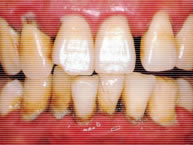

重度歯周炎の歯肉

歯周病がさらに進行すると、歯の支えの多くを失い、骨吸収が歯根長の1/2以上になると歯はぐらつきはじめ、膿が出はじめてくるために口臭もひどくなり、やがて歯が抜けてしまいます。膿が出ることから「歯槽膿漏」とも呼ばれています。歯と歯ぐきの境目を磨き、マッサージする事により、出血、腫れ、赤み、プラークが無くなり、きれいなピンク色の引き締まった歯ぐきに生まれ変わります。プラークコントロールで歯の病気の予防をしましょう。